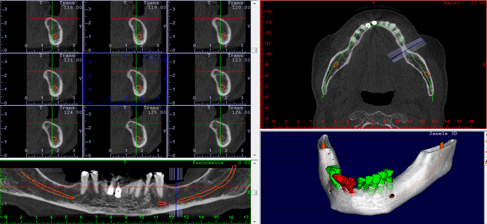

O exame de tomografia cone beam é liberado, em média, em até 3 dias úteis, dependendo da necessidade de urgência. São fornecidas imagens dos cortes tomográfico da região selecionada e as reconstruções 3D que podem ser impressas em papel fotográfico colorido ou filme radiográfico, de acordo com a preferência do profissional. Além dos cortes impressos e o laudo, todo o exame é gravado em um CD contendo o material impresso e um software interativo. Este software possibilita que o dentista planeje virtualmente a colocação de implantes, realize medidas de remanescentes ósseos e localize estruturas anatômicas, ou seja, fornece uma oportunidade única de estudo ao profissional, favorecendo o entendimento e,conseqüente sucesso do tratamento.